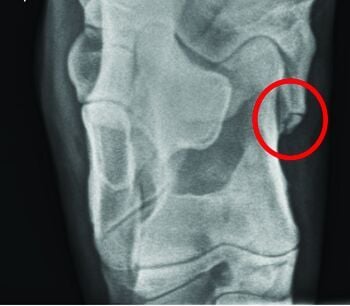

These images were taken recently of a yearling bull that presented for significant hock swelling and grade 3/5 left hind lameness. The circles show a common location of an OCD at the medial malleolus. Images shared with owner permission. Thank you!